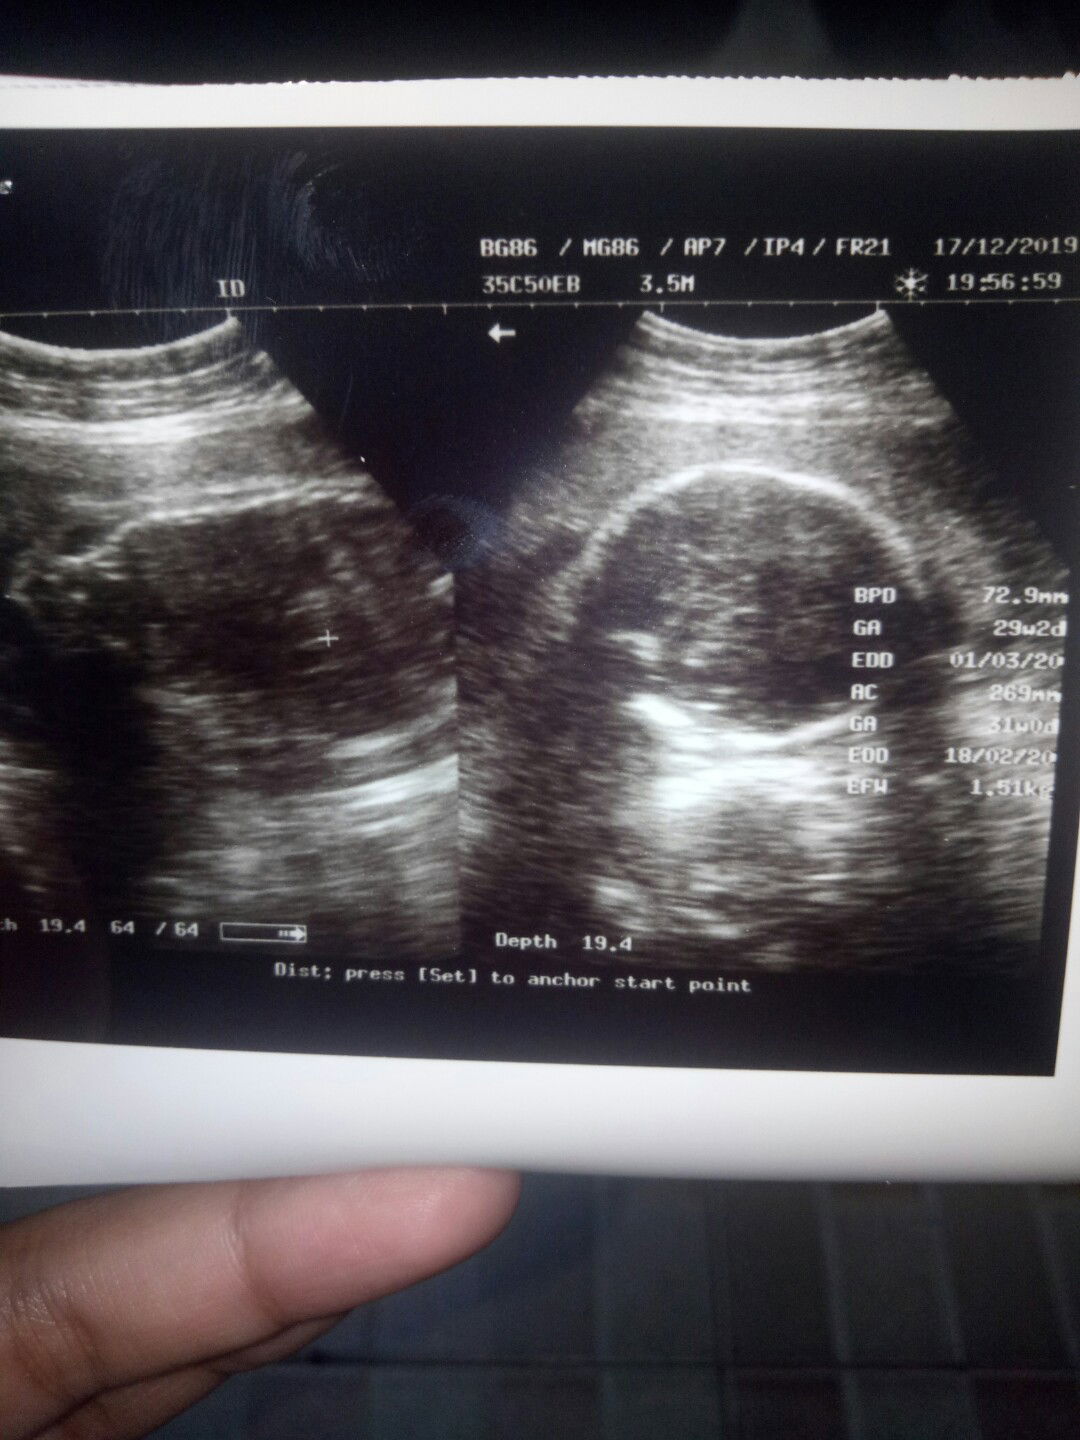

Alhmdulillah hbs usg 29week normal semua bbj 1500kg???